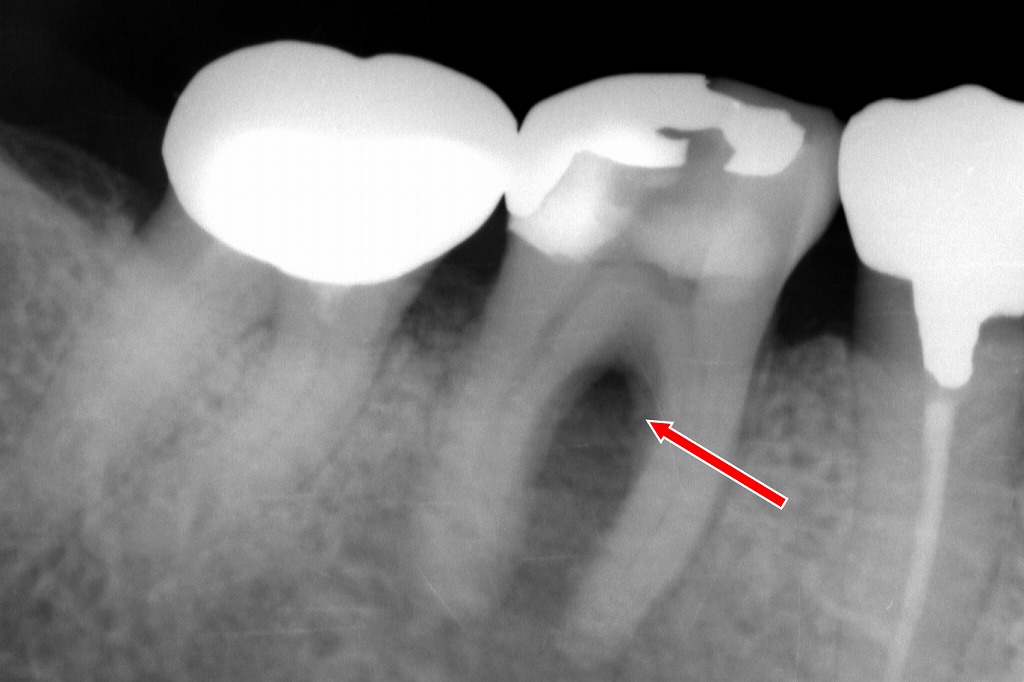

①下顎6番の根分岐部病変

赤矢印の部分に、下顎6番の近心根・遠心根の間(根分岐部)に透過像(黒い部分)が存在しています。

これは**根分岐部病変(furcation involvement)**で、歯髄感染により歯根周囲の骨が溶けている状態を示しています。